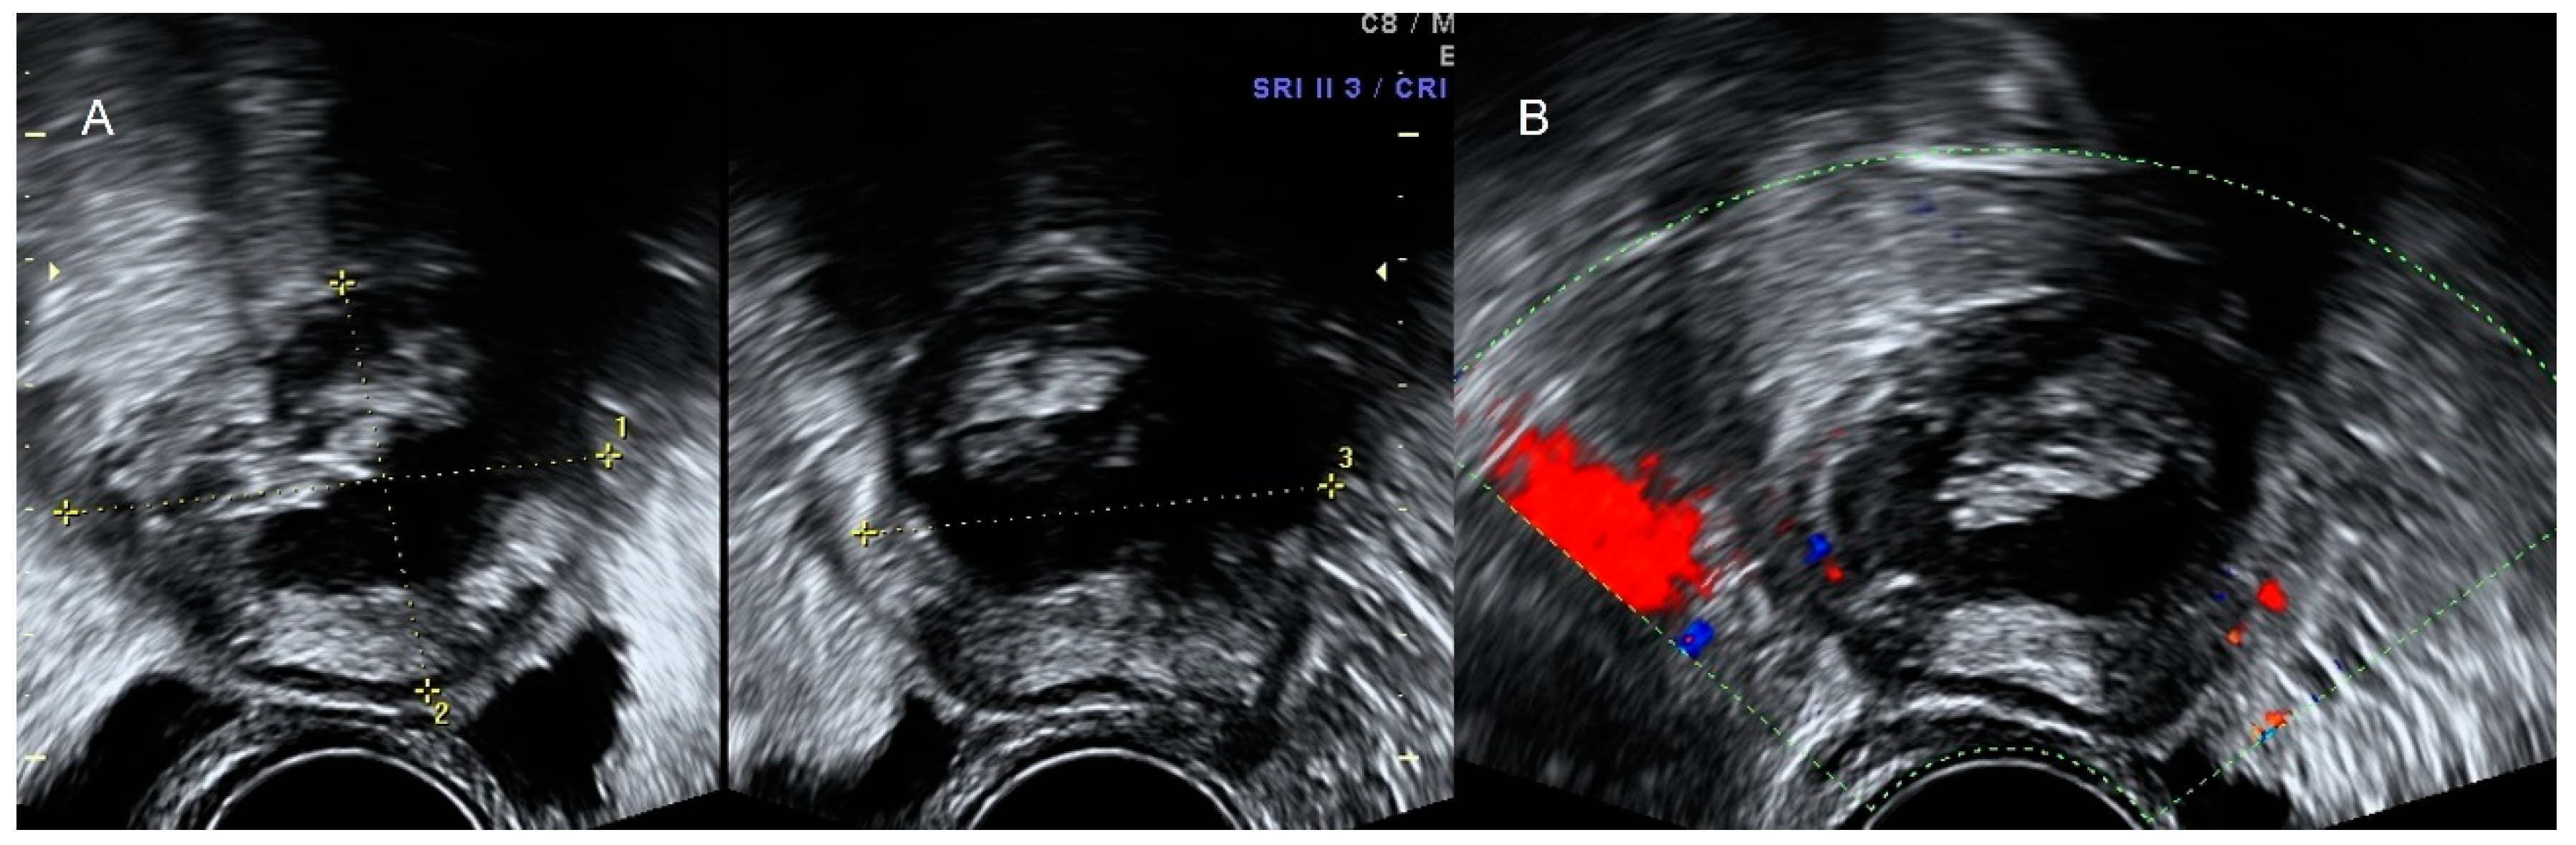

6.2. Neurogenic Tumors: Schwannoma and Neurofibroma